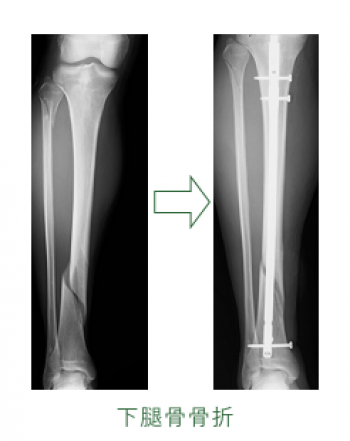

º£Æü¡¢¤´¾Ò²ð¤¹¤ë¤Î¤Ï¡¢²¼Âܹü¹ü´´Éô¹üÀޤˤĤ¤¤Æ¤´¾Ò²ð¤·¤Æ¤¤¤­¤Þ¤¹¡£

²¼Âܹü¹ü´´Éô¹üÀÞ

¸òÄÌ»ö¸Î¡¢¥¹¥Ý¡¼¥Ä¾ã³²¤È¤·¤Æ¤è¤¯¤ß¤ë¹üÀޤǤ¹¡£

¥é¥ó¥Ê¡¼¡¢¥Ð¥¹¥±¥Ã¥È¥Ü¡¼¥ë¡¦¥Ð¥ì¡¼¥Ü¡¼¥ë¤ÎÁª¼ê¡¢¤¦¤µ¤®Ä·¤Ó¤Ê¤É¤Çæú¹ü¤Þ¤¿¤Ï礹ü¤ËÈèÏ«¹üÀÞ¤¬¤ß¤é¤ì¤ë¡£

¿¤¯¤Î¹üÀÞ¤Ïæú¹üÃæ¡¦²¼1/3¤Î¶­³¦Éô¤Ëµ¯¤³¤ê¡¢æú¹ü¤¬¹üÀÞ¤¹¤ë¤È礹ü¤â¤³¤ì¤Ëȼ¤Ã¤Æ¹üÀÞ¤¹¤ë¡£

³«ÊüÀ­¹üÀޤˤʤê¤ä¤¹¤¯¡¢¹üÌþ¹ç¤¬¤·¤Ë¤¯¤¯¡¢È¿Ä¥²¼ÂܤʤɤÎÊÑ·Á¤ò»Ä¤¹¤³¤È¤¬Â¿¤¤¡£

²¼Âܹü¹ü´´Éô¤Î¹üÀޤϡ¢Ç¯Îð¤È¤¤¤¦¤«¸òÄÌ»ö¸Î¡¢¹â½ê¤«¤é¤ÎÍî²¼¡¢¥¹¥Ý¡¼¥Ä¤Ê¤É¤Ë¤è¤ë¤â¤Î¤¬Â¿¤¤¤Ç¤¹¡£